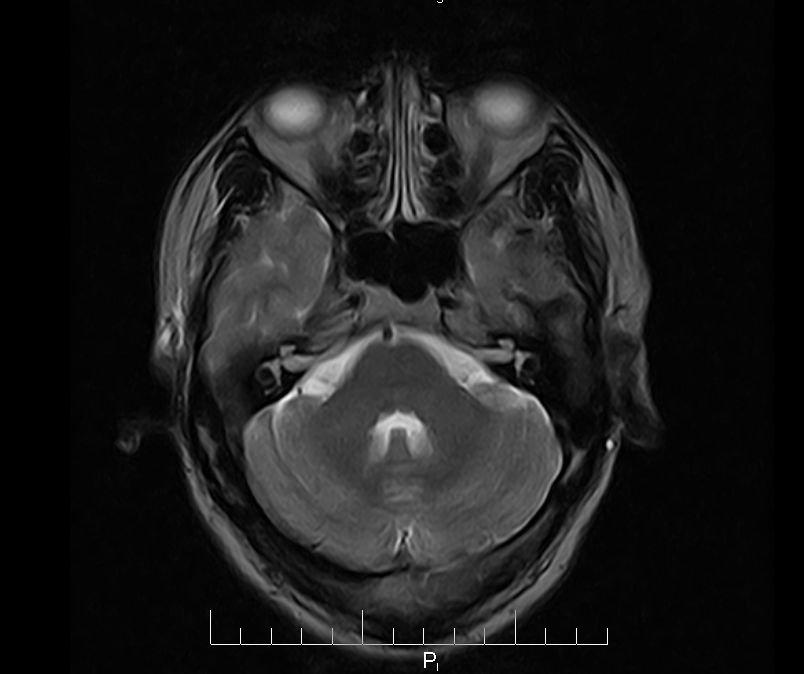

标题: MRI2379:30岁,男,癫痫10年,请各位看一下;CT示:左颞叶钙 [打印本页]

标题: MRI2379:30岁,男,癫痫10年,请各位看一下;CT示:左颞叶钙

左颞叶区见不规则点状混杂信号影

支持2楼 左颞叶区见不规则点状混杂信号影,考虑动静脉畸形。

考虑左侧颞叶脑血管畸形(avm)。----t1低等高混杂信号,t2等高信号周边较多流空血管影[冠状位明显],mra左侧大脑中动脉受压,远侧聚集.